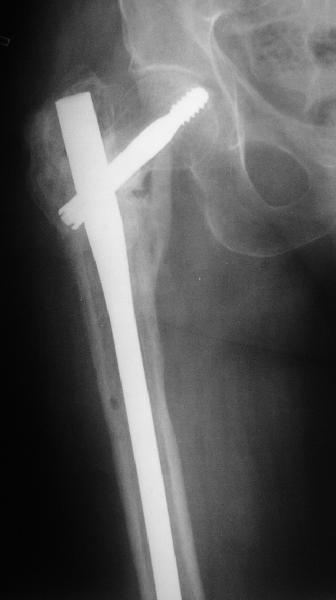

В приложении пример пациента, близкого по картине к тому, что

представил Виктор (варус и смещение периферического отломка на

поперечник кзади). Сделали как раз то, что Виктор исходно намеревался

- аппаратная коррекция и затем гамма.